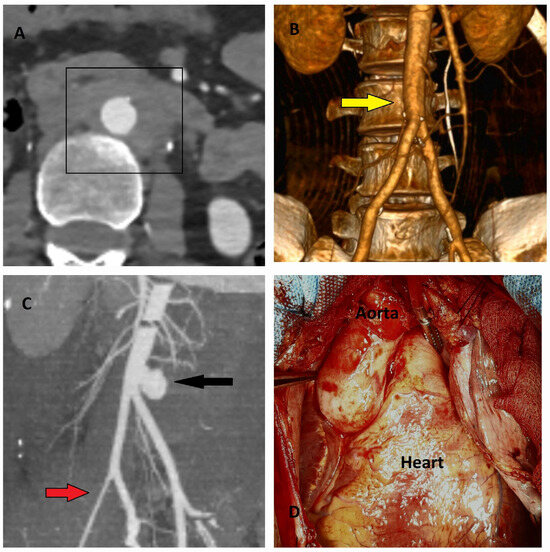

5.2.3. Computed Tomography

5.2.4. Magnetic Resonance Imaging (MRI)